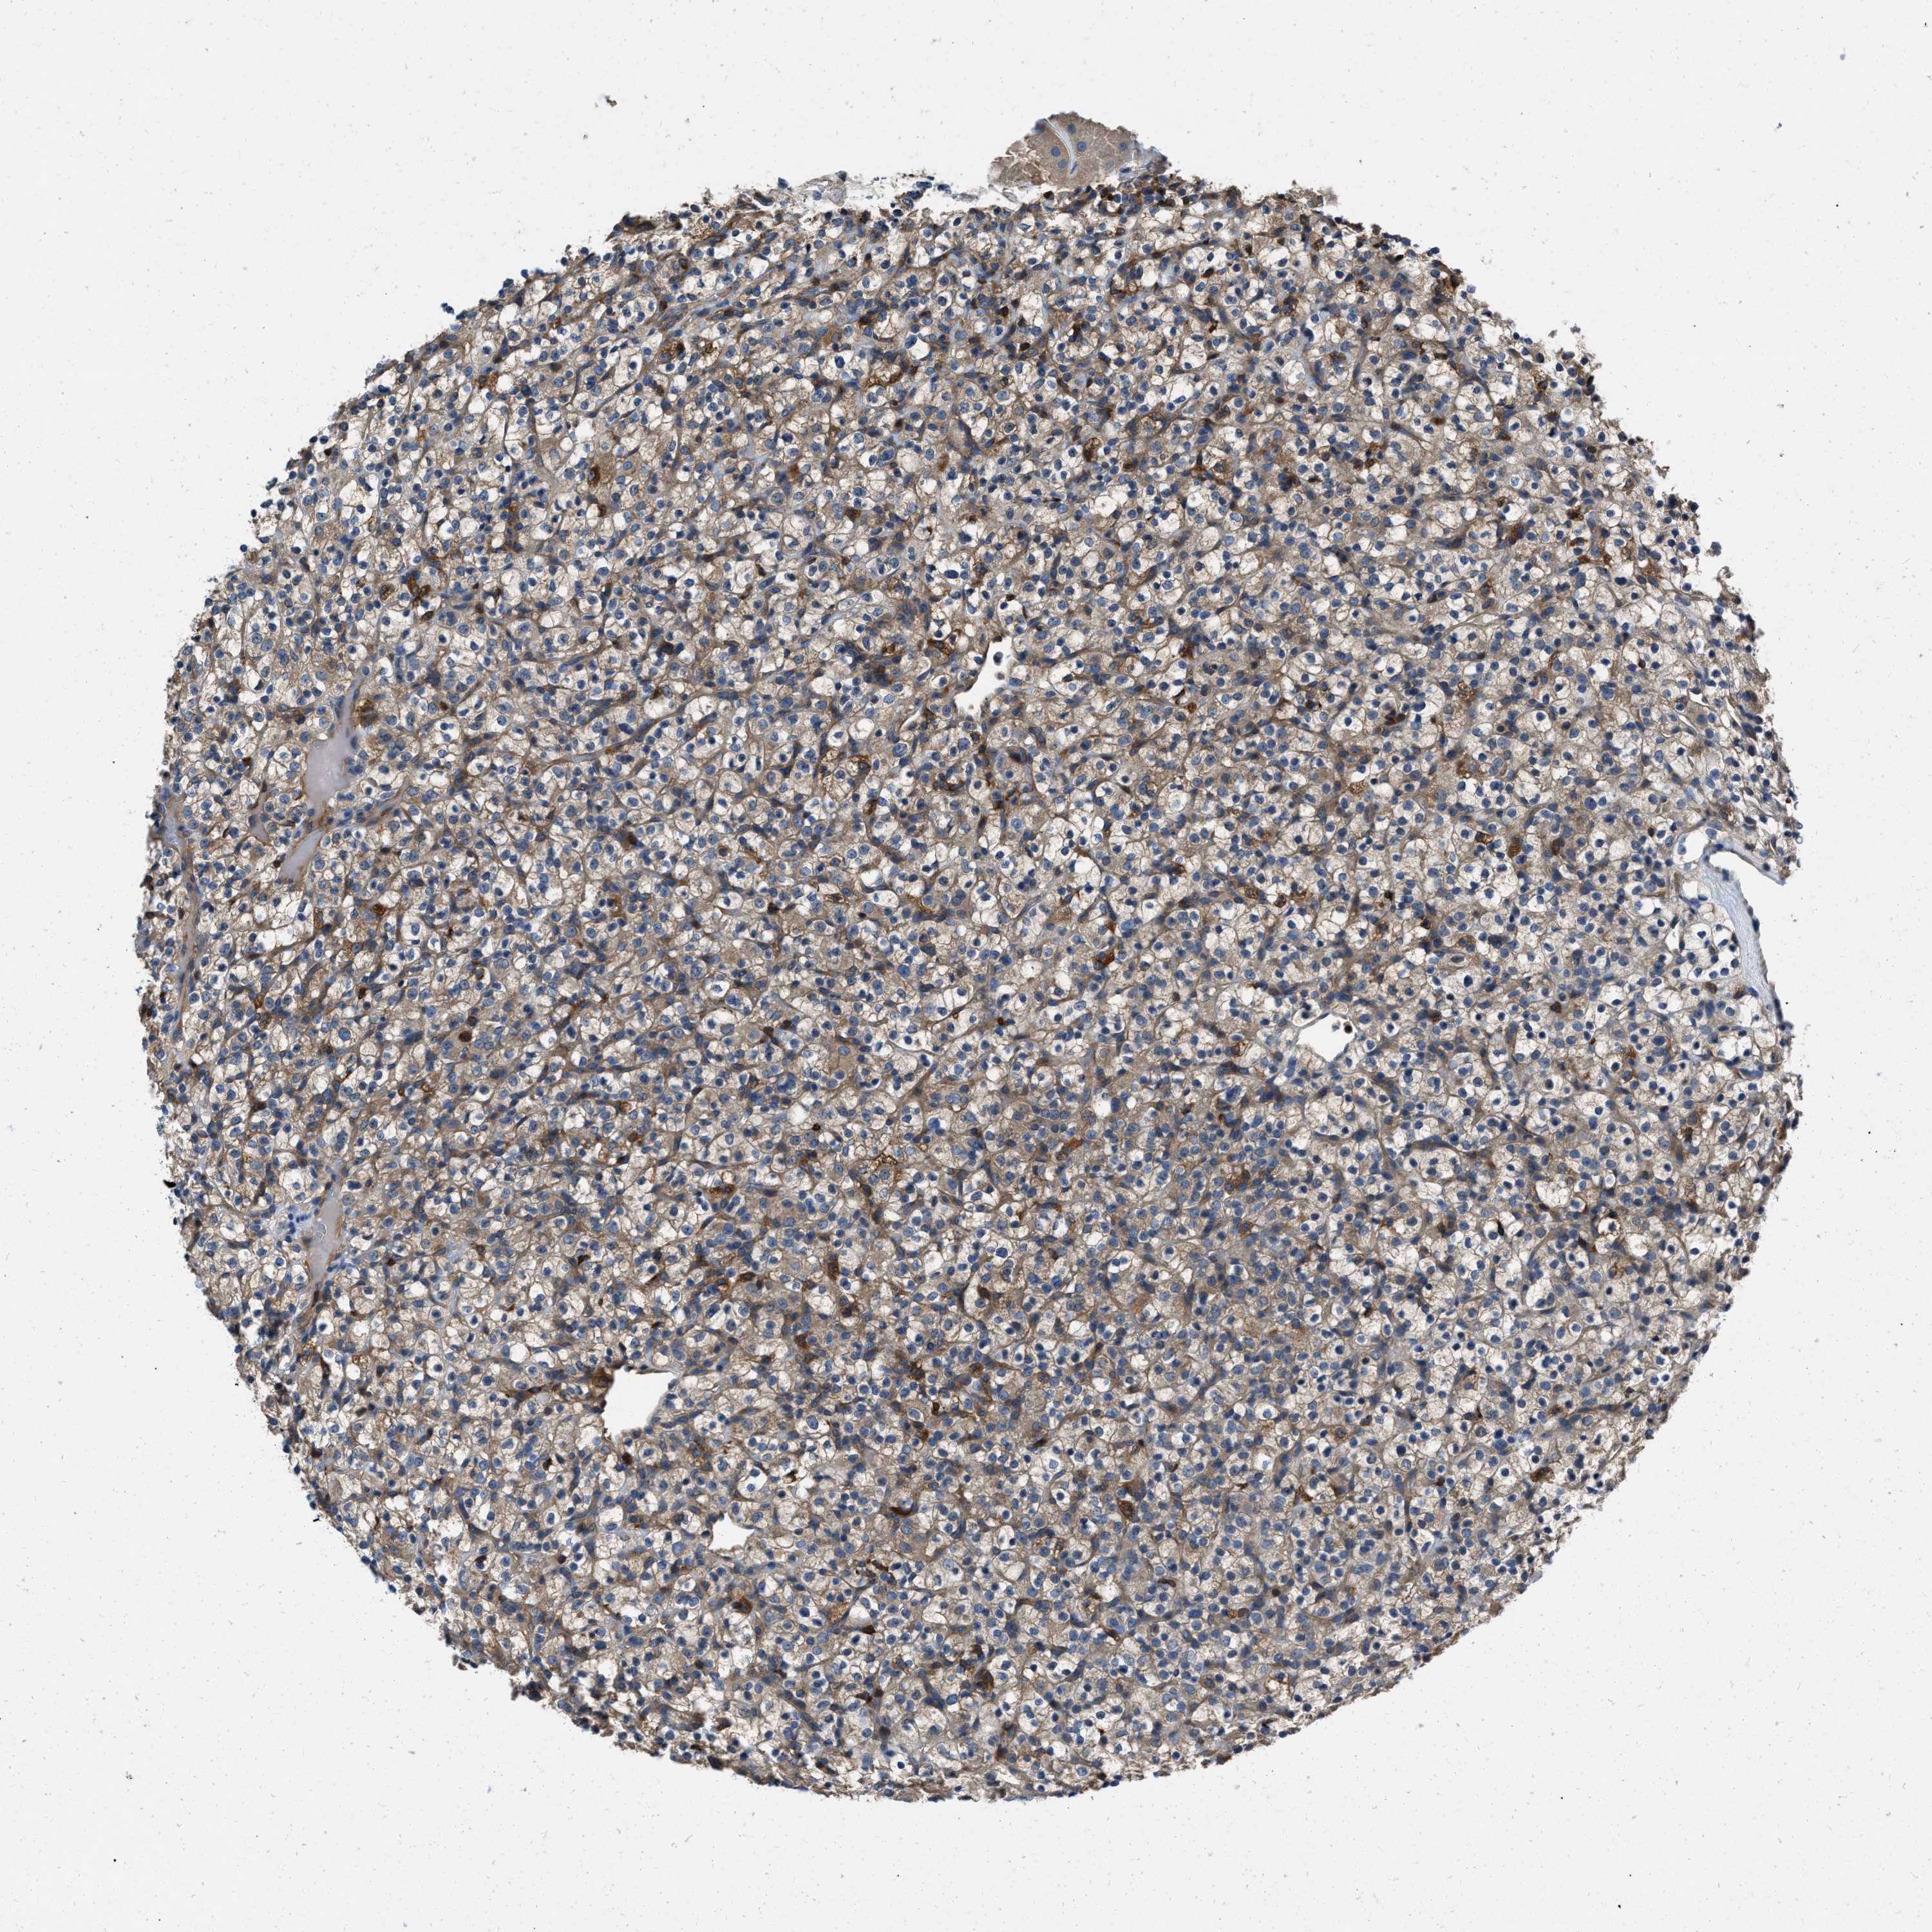

KIDNEY RENAL CLEAR CELL CARCINOMA (TCGA) - Interactive survival scatter ploti

The Survival Scatter plot shows the clinical status (i.e. dead or alive) for all individuals in the patient cohort, based on the same data that underlies the corresponding Kaplan-Meier plots. Patients that are alive at last time for follow-up are shown in blue and patients who have died during the study are shown in red.

The x-axis shows the expression levels (FPKM) of the investigated gene in the tumor tissue at the time of diagnosis. The y-axis shows the follow-up time after diagnosis (years). Both axes are complimented with kernel density curves demonstrating the data density over the axes. The top density plot shows the expression levels (FPKM) distribution among dead (red) and alive patients (blue). The right density plot shows the data density of the survived years of dead patients with high and low expression levels respectively, stratified using the cutoff indicated by the vertical dashed line through the Survival Scatter plot. This cutoff is automatically defined based on the FPKM cutoff that minimizes the p-score. The cutoff can be changed by dragging the vertical line or by entering a cutoff value in the square labeled "Current cut-off".

Under the Survival Scatter plot the p-score landscape (black curve; left axis) is shown together with dead median separation (red curve; right axis). Dead median separation is the difference in median mRNA expression between patients who have died with high and low expression, respectively. It is calculated as follows: median FPKM expression of dead patients with high expression - median FPKM expression of dead patients with low expression. This is intended to aid the user in visually exploring custom cutoffs and the associated p-scores and dead median separation.

Individual patient data is displayed and can be filtered by clicking on one or more of the category buttons on the top of the page. Categories describing expression level and patient information include: high, low, alive, dead, female, male and tumor stages. The scale of the x-axis can be toggled between linear and log-scale by clicking on the "x log" button. Mouse-over function shows TCGA ID, patient information and mRNA expression (FPKM) for each patient.

& Survival analysisi

Kaplan-Meier plots summarize results from analysis of correlation between mRNA expression level and patient survival. Patients were divided based on level of expression into one of the two groups "low" (under cut off) or "high" (over cut off). X-axis shows time for survival (years) and y-axis shows the probability of survival, where 1.0 corresponds to 100 percent.

YARS1 is not prognostic in Kidney Renal Clear Cell Carcinoma (TCGA)

Best expression cut offi

Based on the FPKM value of each gene, patients were classified into two groups and association between prognosis (survival) and gene expression (FPKM) was examined. The best expression cut-off refers the FPKM value that yields maximal difference with regard to survival between the two groups at the lowest log-rank P-value. Best expression cut-off was selected based on survival analysis .

When clicking on this number, the vertical dashed line indicating cut-off, the interactive survival plot, and the Kaplan-Meier curve will be adjusted to show results based on the best expression cut-off.

: 24.39

P scorei

Log-rank P value for Kaplan-Meier plot showing results from analysis of correlation between mRNA expression level and patient survival.

N/A

TCGA RNA samplesi

RNA-seq data is reported as average FPKM (number Fragments Per Kilobase of exon per Million reads), generated by the The Cancer Genome Atlas (TCGA) .

Normal distribution across the dataset is visualized with box plots, shown as median and 25th and 75th percentiles. Points are displayed as outliers if they are above or below 1.5 times the interquartile range. FPKM values of the individual samples are presented next to the box plot.

Average pTPM 33.1

Number of samples 521